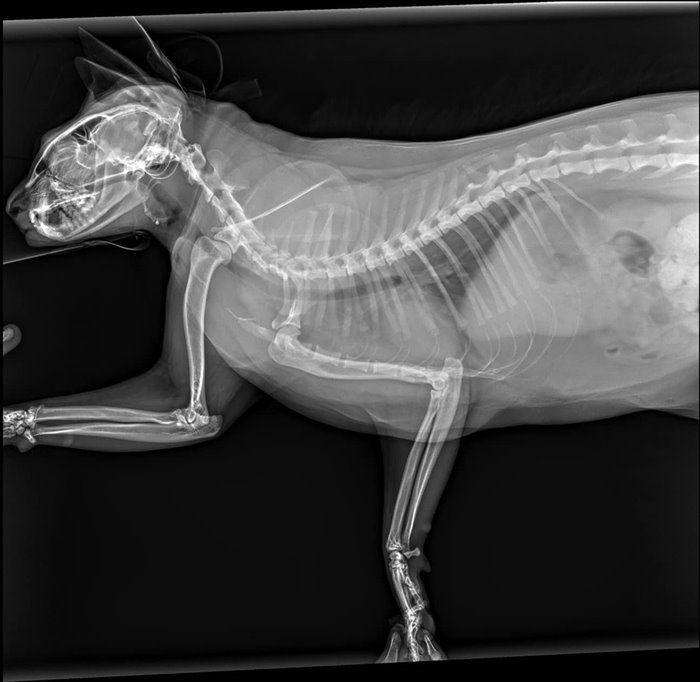

วันที่ 28 พฤษภาคม 2566 สรยุทธ สุทัศนะจินดา รายงานว่า ได้มีการอัปเดตอาการ น้องซิฟู เหมียวน้อยตัวดังกล่าวว่า "อัปเดตอาการน้องซิฟู หรืออาจารย์ซิฟู ในกังฟูแพนด้านั่นเอง น้องปกติทุกอย่าง กินข้าวได้ อึขับถ่ายปกติ ไม่มีอาการบวมหรือช้ำในใด ๆ มีเพียงแค่เล็บหลุด 2 นิ้ว และเป็นห้อเลือดเท่านั้นครับ"